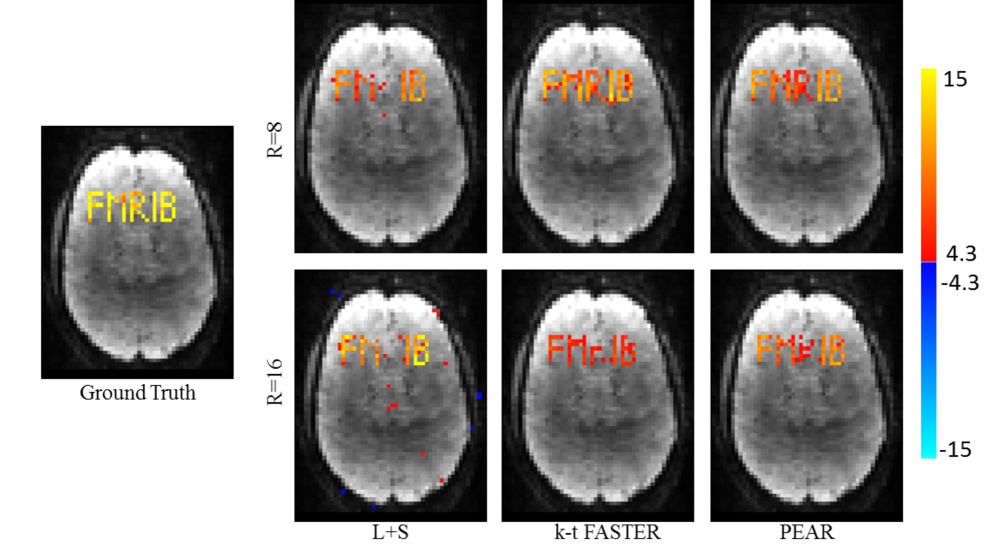

To examine the correspondence of the reconstruction with the ground-truth, we performed regression against the original timecourses using General Linear Model (GLM)Jenkinson et al. [2012]. Figure 3 shows the F-test results as null-corrected z-statistics mapsBeckmann et al. [2005], for the ground-truth data (fully sampled image without the addition of noise), L+S, k-t FASTER and PEAR, for both R=8 and R=16. All maps are thresholded at and shown with color scale mapped between .

It can be seen that PEAR provides the most reliable result, being the only method that almost perfectly recovers both “M” and “B” with minimum false positive errors at R=16. In addition, we see that L+S is unable to recover the aperiodic timecourse “R”, as opposed to both k-t FASTER and PEAR thanks to their fixed-rank component.

Figure 6 shows the General Linear Model (GLM) F-test Jenkinson et al. [2012] results as null-corrected z-statistics maps that were computed against the realistic time courses of all letters, for the ground-truth data (fully sampled image without the addition of noise), L+S, k-t FASTER and PEAR, for R=8 and R=16. All maps are thresholded at and shown with color scale mapped between .

In correspondence with experiment 1, for realistic timecourses we see that for R=8, both k-t FASTER and PEAR provide similar results that outperform L+S. For R=16, we see that PEAR provides cleaner results, as can be seen mainly when comparing the recovery of the letters “F” and “B”. It can also be seen that all methods are unable to recover “R” and “I” due to the high undersampling ratio. It can also be seen that “R” and “I” are the letters with the lowest Z values in the fully-sampled, ground truth data, due to their low energy in this experiment.